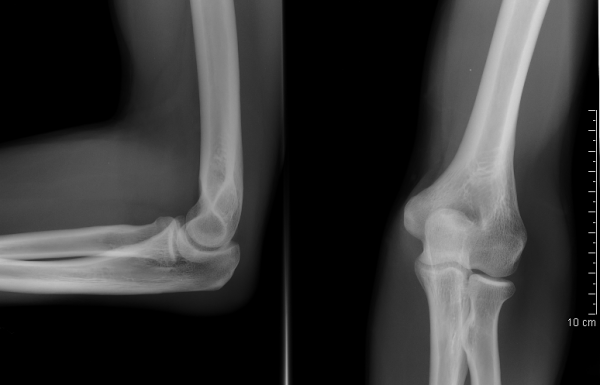

Простые рентгенограммы

МРТ/КТ для дальнейшей оценки

Диагностические процедуры